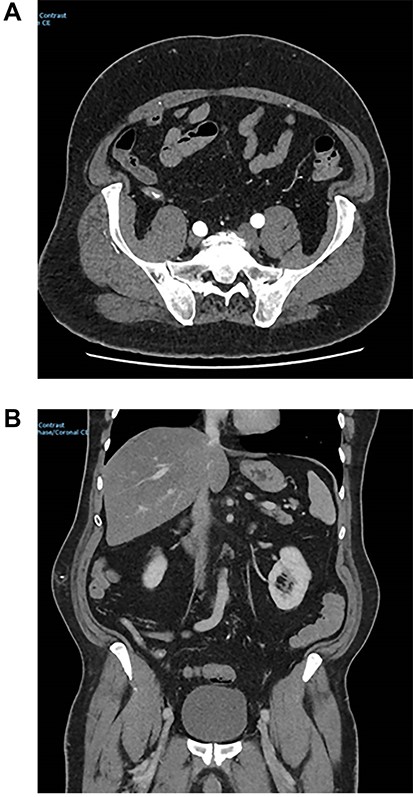

At angiogram, the superior mesenteric artery (SMA) was successfully cannulated, and the patient was found to have active extravasation from the appendiceal artery (Fig. 2). This was successfully controlled with a 3 mm coil.

Images from angiography. (A) Pre-embolization, demonstrates appendiceal lumen filled with contrast. (B) Demonstrated coiled artery.